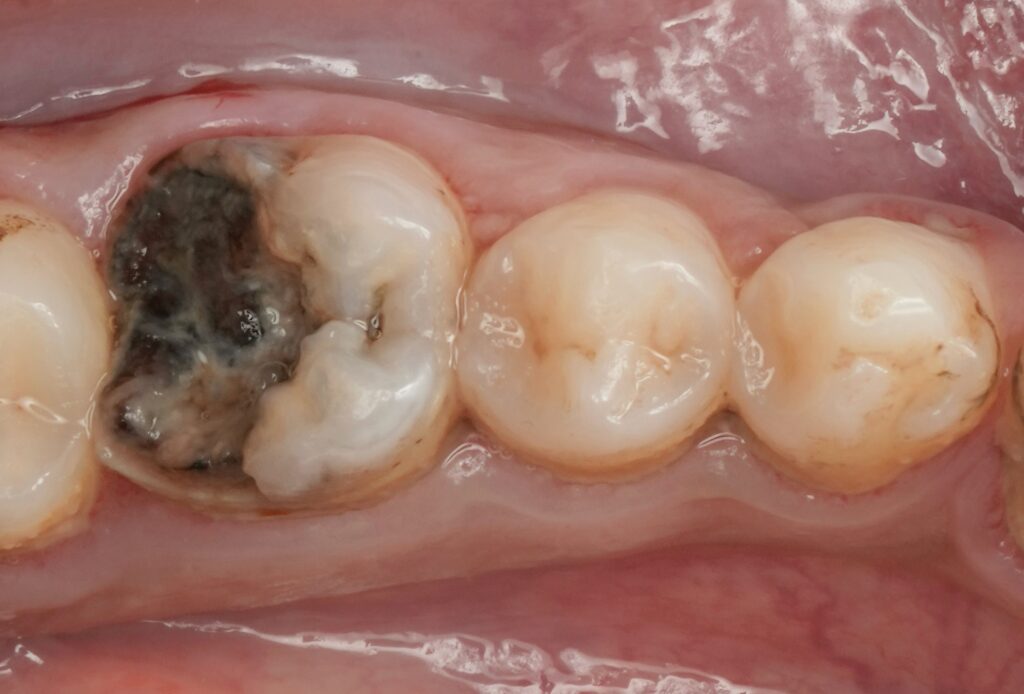

Diagnosis and Treatment Planning

Clinical findings:

- Extensive distal caries on mandibular first molar

- Subgingival proximal margin

- Pulpal involvement

- Tenderness on percussion

- Radiographic evidence of deep carious lesion approaching pulp